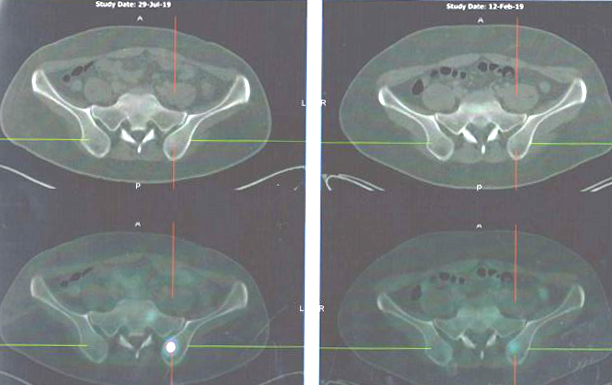

Let us look at the results of his PET scan.

Comparison of scan results: 29 July 2019 (top row) vs 12 February 2019 (bottom row)

Comparison of scan results: 29 July 2019 (left row) vs 12 February 2019 (right row)

Something wrong with the bones? Scan on 29 July 2019 (left column) seemed to be more serious than scan done on 12 Feb 2019 (right).

Did the cancer go away after all the treatments?

Again, ask this question: From the above, do you see any improvement? And what had scientific, modern medicine done to him? Study what the reports carefully and you will know the answers.